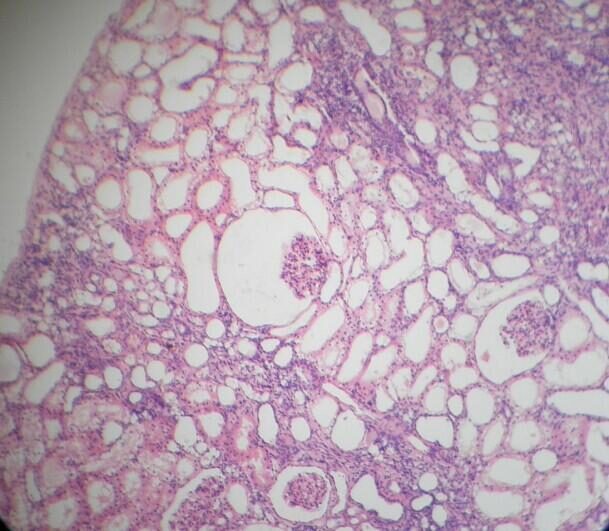

Микропрепараты: Лимфогранулематоз и Нодулярный Склероз

Раздел: Секреты мастерства